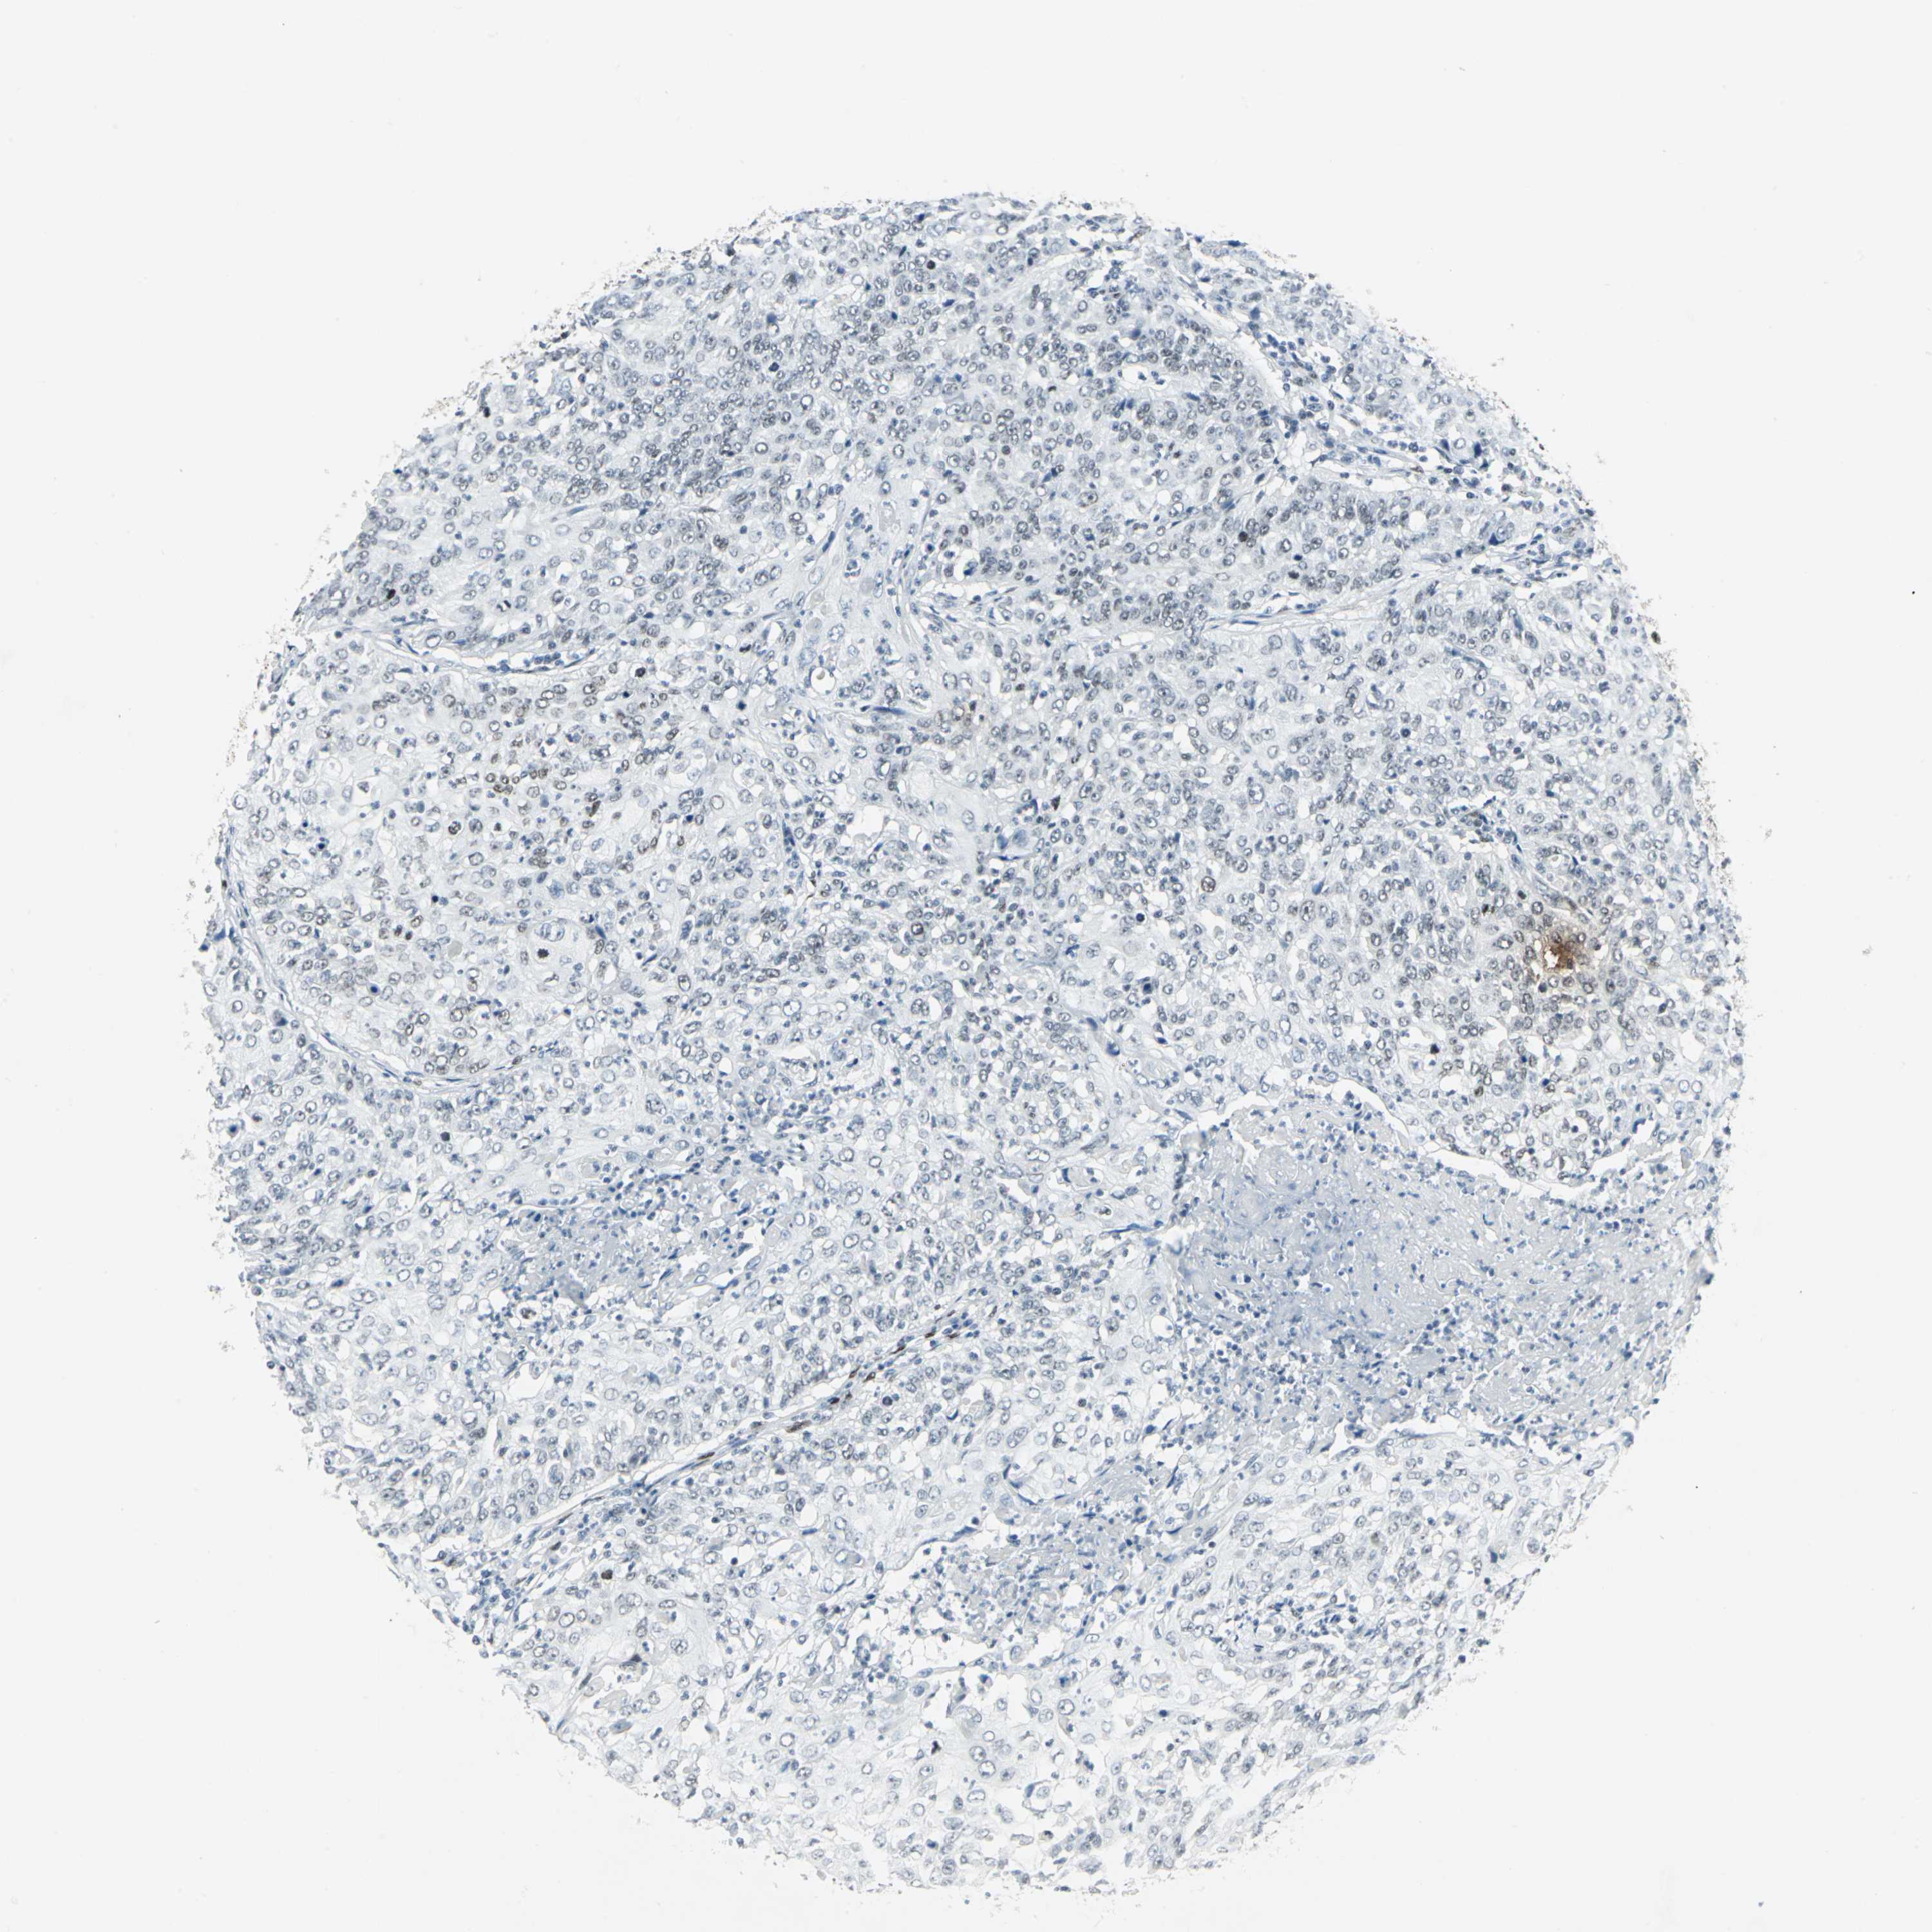

CERVICAL CANCER - Protein expressioni

A mouse-over function shows sample information and annotation data. Click on an image to view it in a full screen mode. Samples can be filtered based on level of antibody staining by selecting one or several of the following categories: high, medium, low and not detected. The assay and annotation is described here.

Antibody stainingi

Antibody staining in the annotated cell types in the current human tissue is reported as not detected, low, medium, or high, based on conventional immunohistochemistry profiling in selected tissues. This score is based on the combination of the staining intensity and fraction of stained cells.

Each image is clickable and will lead to virtual microscopy that enables deeper exploration of all samples and also displays staining intensity scores, fraction scores and subcellular localization as well as patient and tissue information for each sample.

Antibody HPA003256

Staining

High

Intensity

Strong

Quantity

>75%

Location

Nuclear

Squamous cell carcinoma, NOS